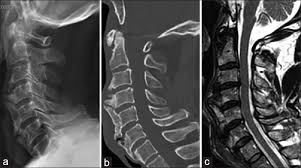

(opll stands for ossification of the posterior longitudinal ligament.

Ossification Of The Anterior Longitudinal Ligament And Forestier S Disease An Analysis Of Seven Cases In Journal Of Neurosurgery Volume 83 Issue 1 1995

Ossification Of The Anterior Longitudinal Ligament And Forestier S Disease An Analysis Of Seven Cases In Journal Of Neurosurgery Volume 83 Issue 1 1995 from thejns.org